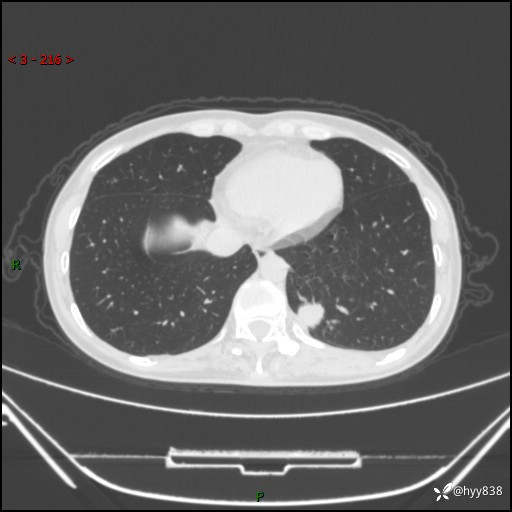

增强动脉期+静脉期

各期CT值:48hu 65hu 76hu